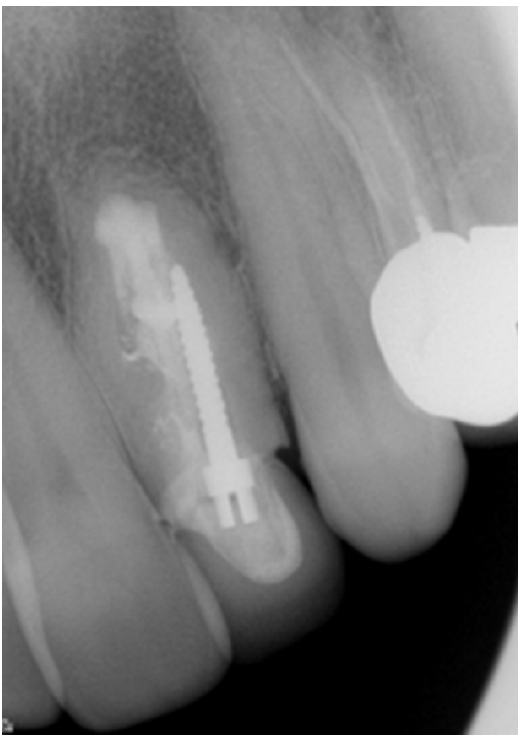

Thirty years later (2002), the patient came back to the department with a complaint of pain and swelling and was diagnosed with an acute apical abscess in tooth #22. Informed consent was obtained and endodontic surgery was performed in the department (Figure 2). The tooth was treated with a modern surgical endodontic protocol, involving a dental operating microscope: local anesthesia with lidocaine 2% with epinephrine 1:100,000, triangular full mucoperiosteal flap, osteotomy, root-end resection with no bevel using a high-speed bur, curettage, retrograde preparation using ultrasonic tips, and root-end filling with intermediate restorative material (IRM; L.D. Caulk Company, Milford, DE, USA).

Clinical and radiographic follow-up was scheduled annually. Radiographic outcomes were assessed based on the criteria established by Rud et al. [17]. At a 2-year follow-up, the tooth was clinically asymptomatic, with good adaptation of the crown to the tooth and with radiographically normal periapical tissue (Figure 2C). The tooth remained asymptomatic with radiographically complete healing at an additional follow-up visit in 2006 (Figure 2D).

Endodontic surgery on tooth #22. (A) Preoperative radiograph in 2002 showing periapical radiolucent area around the apex and distal aspect of the root. Note the excess filling material outside the root. At the time of referral, the tooth had been restored with a post and crown. Marginal defects can be seen in the final restoration. (B) Intraoperative photograph in 2002. (C) Postoperative radiograph in 2002. The apical part of the mesial cavity was prepared and filled. Excess filling material that was outside the root was removed. (D) Four-year follow-up radiograph in 2006 showing complete healing with no periapical radiolucency present.

Figure 2. Endodontic surgery on tooth #22. (A) Preoperative radiograph in 2002 showing periapical radiolucent area around the apex and distal aspect of the root. Note the excess filling material outside the root. At the time of referral, the tooth had been restored with a post and crown. Marginal defects can be seen in the final restoration. (B) Intraoperative photograph in 2002. (C) Postoperative radiograph in 2002. The apical part of the mesial cavity was prepared and filled. Excess filling material that was outside the root was removed. (D) Four-year follow-up radiograph in 2006 showing complete healing with no periapical radiolucency present.